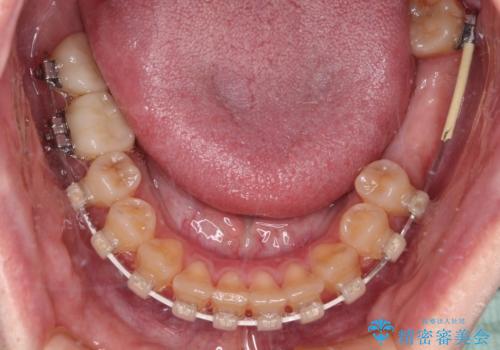

まずはむし歯の治療を行い、その後ワイヤー矯正にて咬み合わせを改善し、途中インプラント埋入を行い、矯正治療後に補綴治療を行うこととしました。